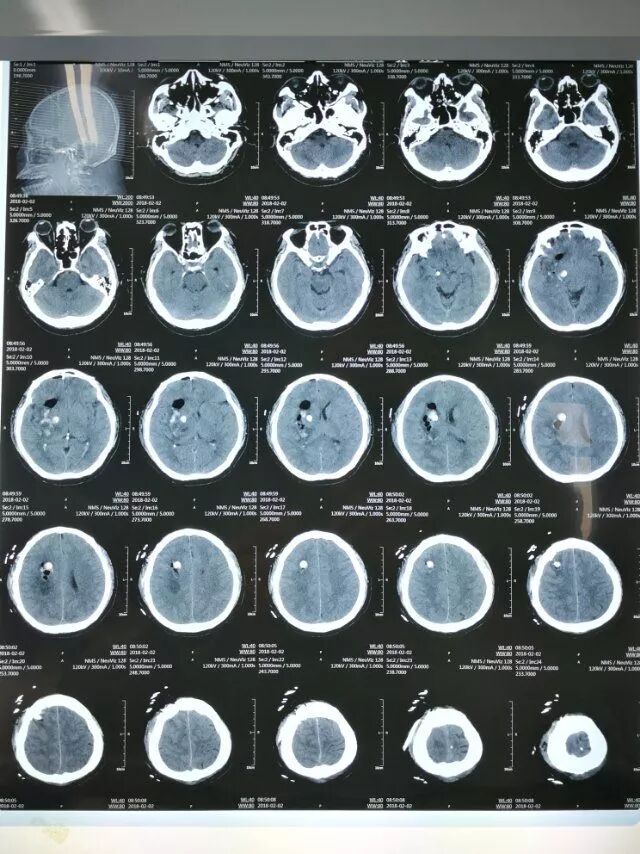

患者男性,48岁,脑出血发病2小时入院。神志模糊,继发脑疝,头CT:右侧基底节出血量约60毫升。

术后第一天复查